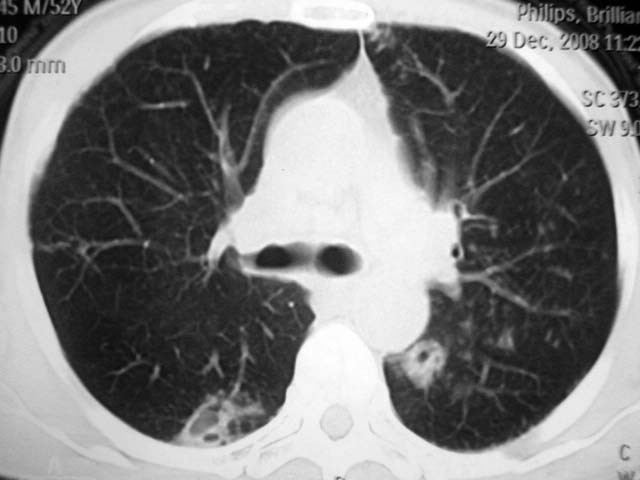

男,52岁,发热2月,糖尿病史。

抗结核治疗irpz方案,血糖未治疗,空腹15.9左右。症状无好转,左胸痛。

2、双肺见多发片状及结节状高密度影,大多数病灶中心均见“空泡征”。

3、纵隔内淋巴结肿大。

结果:两肺继发性肺结核并曲霉菌感染。